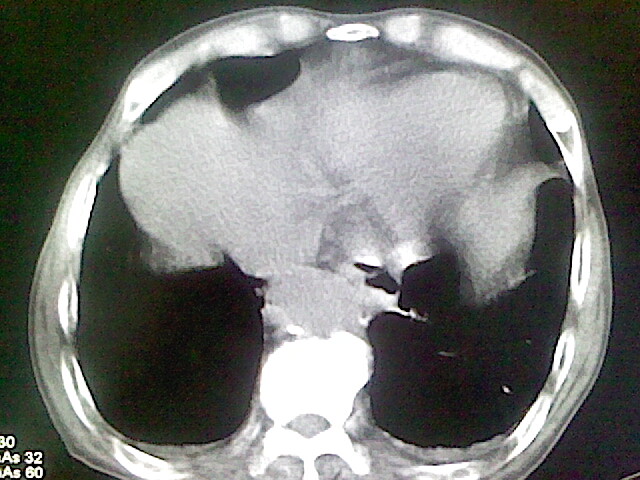

以下是引用zsl6918在2008-8-28 16:49:00的发言:[br]双肺炎性病灶,食管狭窄估计与心房增大压迫所致。

以下是引用xulianj在2008-8-28 20:36:00的发言:[br]慢支肺气肿伴感染,右上肺陈旧性结核;食道建议胃镜检查。

以下是引用wqs571018在2008-8-28 21:18:00的发言:[br]慢支继发感染,右上肺陈旧性结核;食道建议胃镜检查。